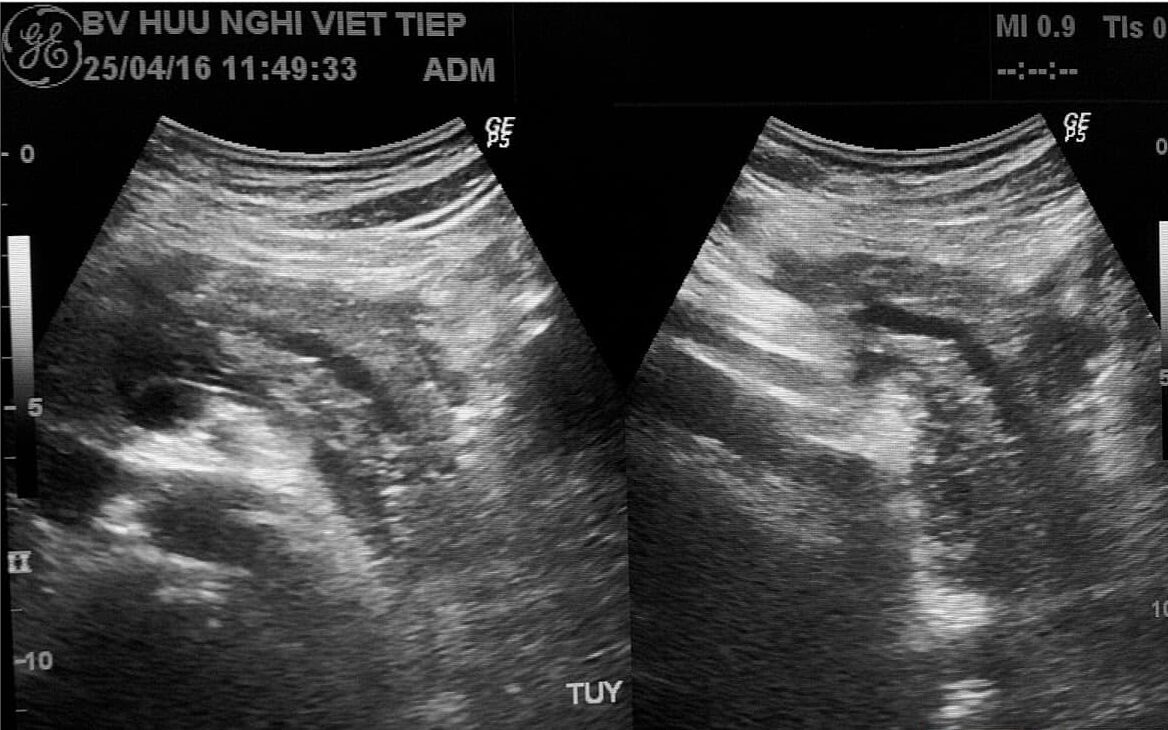

– Viêm tụy cấp (Acute pancreatitis) là một quá trình viêm cấp tính của tụy, biểu hiện ở nhiều mức độ khác nhau. Có hai dạng chính của viêm tụy cấp theo phân loại Atlanta sửa đổi:

+ Viêm tụy cấp phù nề (Interstitial edematous pancreatitis): chiếm phần lớn các trường hợp (90-95%), thường được gọi đơn giản là viêm tụy cấp hoặc “viêm tụy không biến chứng”.

+ Viêm tụy hoại tử (Necrotizing pancreatitis): gây hoại tử mô tụy và/hoặc mô quanh tụy, hoại tử có thể vô trùng hoặc nhiễm trùng, với nhiễm trùng thường gây biến chứng nghiêm trọng. Khoảng 5-10% bệnh nhân bị viêm tụy cấp phù nề có thể tiến triển thành viêm tụy hoại tử. khoảng 40% trường hợp viêm tụy hoại tử bị nhiễm trùng, thường sau tuần đầu tiên.

– Viêm tụy cấp thể phù:

+ Tụy sưng phù, phù có thể chỉ ở tụy hoặc lan ra mô liên kết sau phúc mạc, mạc nối. Trong ổ bụng có thể thấy nhiều hay ít dịch loại thanh dịch. Tiến triển có thể khỏi hoàn toàn hoặc dẫn tới viêm tụy cấp hoại tử.